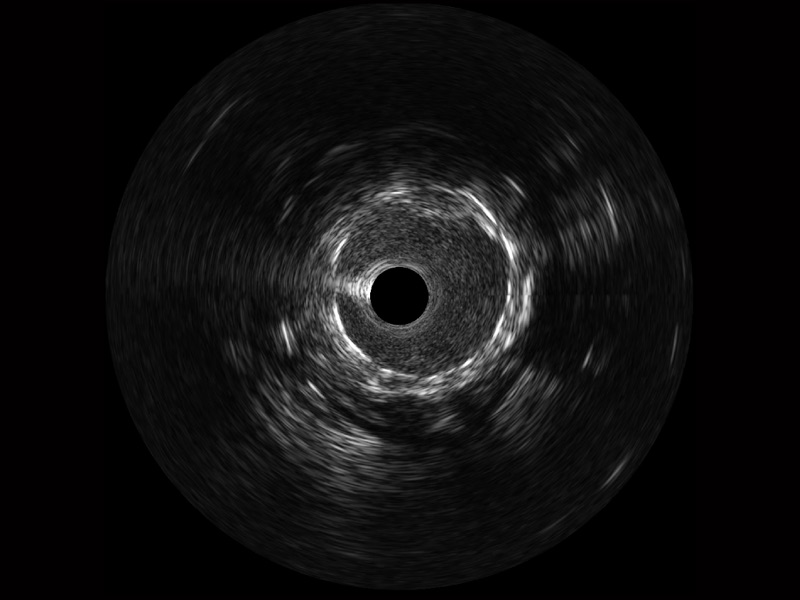

• 百老汇电子游戏官网宽频IVUS图像

• 传统IVUS图像

对比传统IVUS导管成像,百老汇电子游戏官网宽频IVUS图像的近场支架梁显影更细腻,远场中膜外血管仍清晰可辨,兼顾远中近,兼顾分辨力与穿透深度